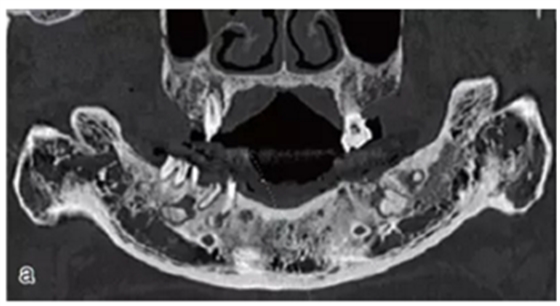

術(shù)前拍攝錐形束CT,進(jìn)行三維重建和種植方案規(guī)劃。從CT圖像中可以看出頜骨內(nèi)有骨島和殘根,為避免種植體植入骨島區(qū),考慮在兩側(cè)頦孔區(qū)種植4~5顆種植體,采用套筒冠進(jìn)行即刻修復(fù)。從重建的結(jié)果中可知前牙區(qū)牙槽嵴呈刀刃狀。種植方案為:對前牙區(qū)牙槽嵴進(jìn)行截骨修整,并在兩頦孔之間的區(qū)域內(nèi)植入5顆種植體。

圖15 種植方案的規(guī)劃:a.患者的CT圖像的截面圖,圈紅處為骨島;b.患者摘掉活動義齒后的下頜;c.患者上下頜骨的CT三維重建;d.下頜骨截骨后模擬植入5顆種植體